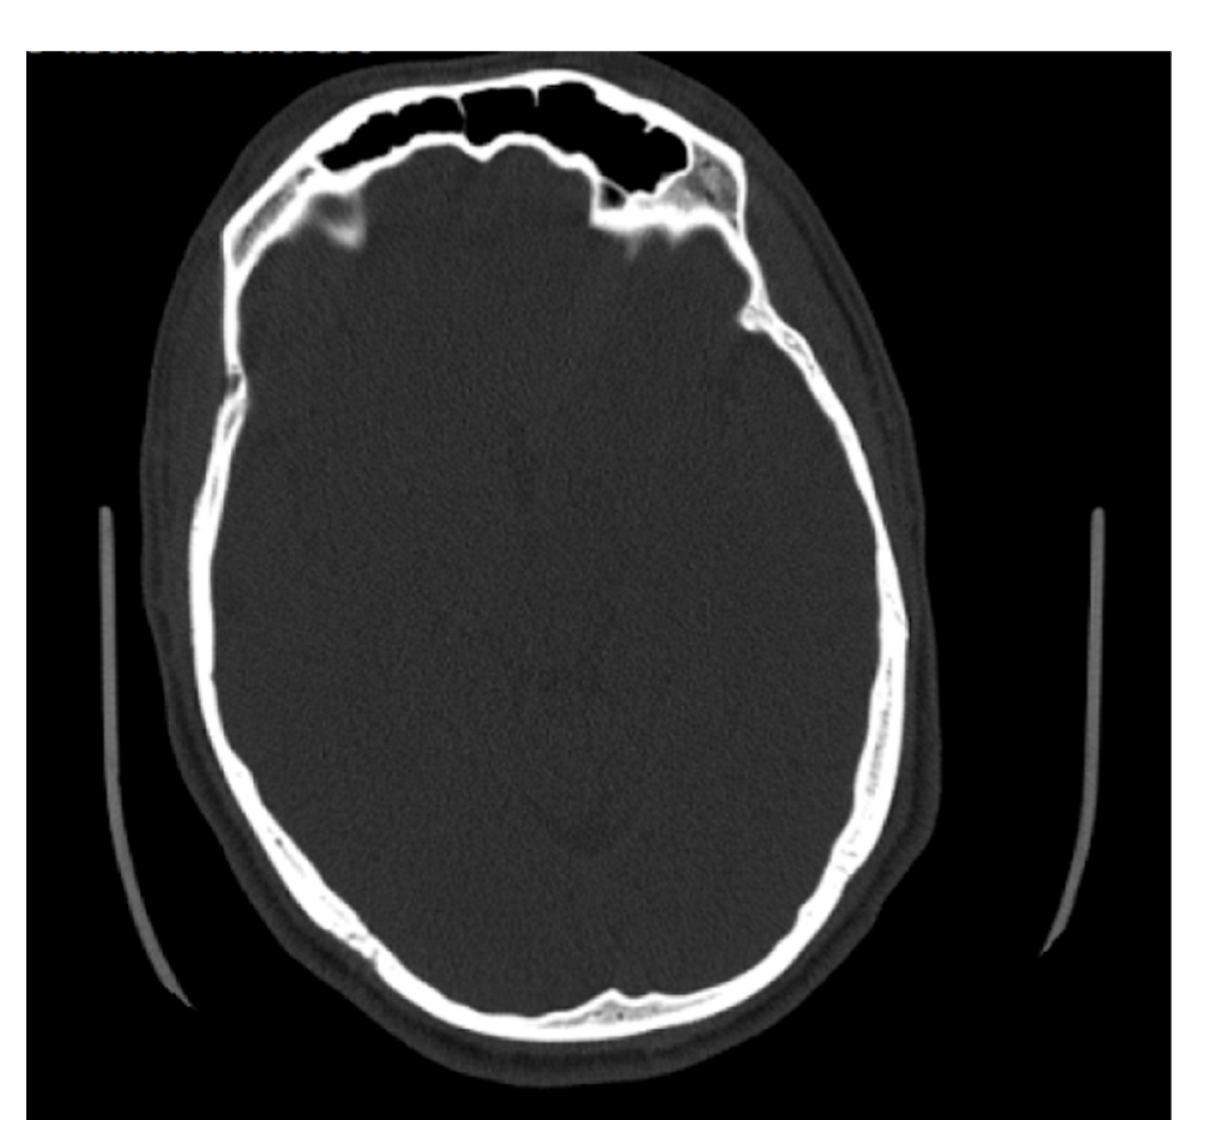

4.1. Frontal Sinus Absence and Unilateral Expression